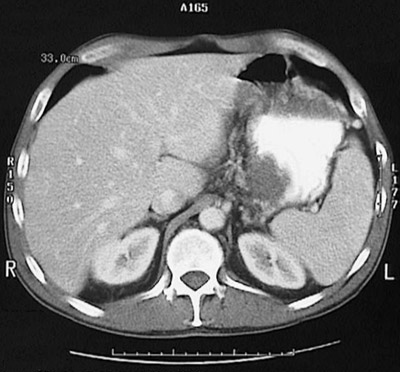

Image 7.4 A cystic space in the lesser sac lined by inflamed, necrotic tissue is seen here. In the abdominal CT scan view below, this cystic area appears with a low attenuation liquefied center, involving the tail of the pancreas, that appears to interdigitate with accentuated gastric rugal folds of the stomach filled with bright contrast. |